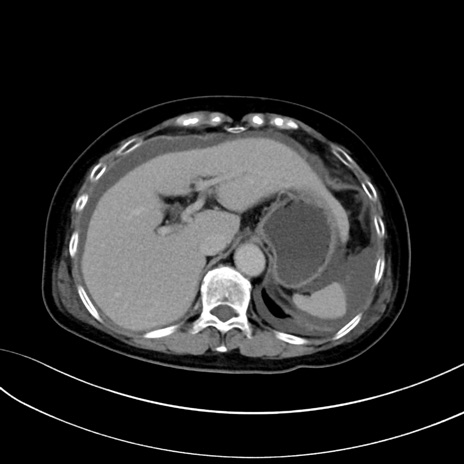

症例13 CT(横断像)1日半後